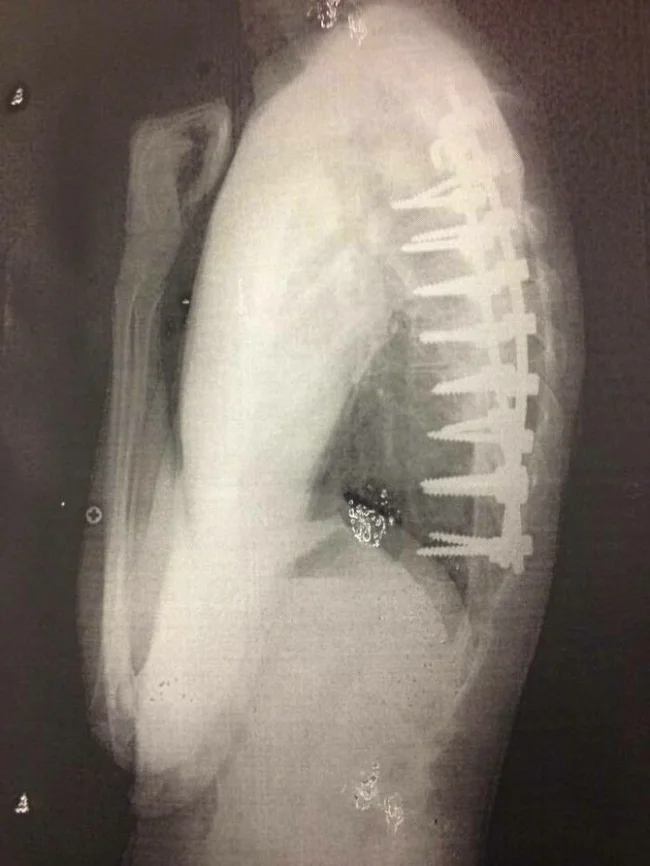

23. Эти винты казались мне гораздо меньше